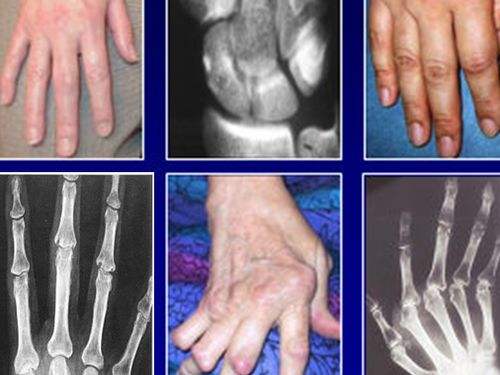

風(fēng)濕性關(guān)節(jié)炎常見累及大關(guān)節(jié)(膝關(guān)節(jié)、肘關(guān)節(jié)等),不造成關(guān)節(jié)的畸形。還有環(huán)形紅斑、舞蹈癥、心臟炎的癥狀。類風(fēng)濕關(guān)節(jié)炎往往侵犯小關(guān)節(jié)(尤其是掌指關(guān)節(jié)、近端指間關(guān)節(jié)、腕關(guān)節(jié)),也會(huì)侵及其他大小關(guān)節(jié),晚期往往造成關(guān)節(jié)的畸形。

5.手部有典型的類風(fēng)濕性關(guān)節(jié)炎的放射學(xué)改變。